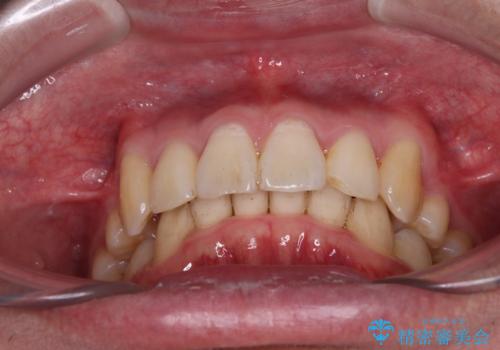

- 八重歯を気にして来院された患者様です。

顕著な上顎の八重歯とディープバイトであったため、上顎の左右第一小臼歯を抜歯することとしました。

犬歯歯根の位置や奥歯の咬み合わせから、ワイヤー装置での治療を強くおすすめいたしましたが、ご本人の強い希望により、妥協的な仕上がりとなることを了解いただき、インビザラインにて矯正治療を行うこととしました。

インビザライン単体で、左右ともに移動の難しい位置に歯根のある犬歯を整えるのは困難と判断し、補助装置を併用することとしました。

ディープバイトや奥歯の咬み合わせなど、インビザライン矯正では限界がありワイヤー装置での治療に及ばない仕上がりとなりました。

ただし、患者様としては八重歯や、それに伴う唇の閉じにくさが改善されたとのことで、納得いく状態での治療終了となりました。